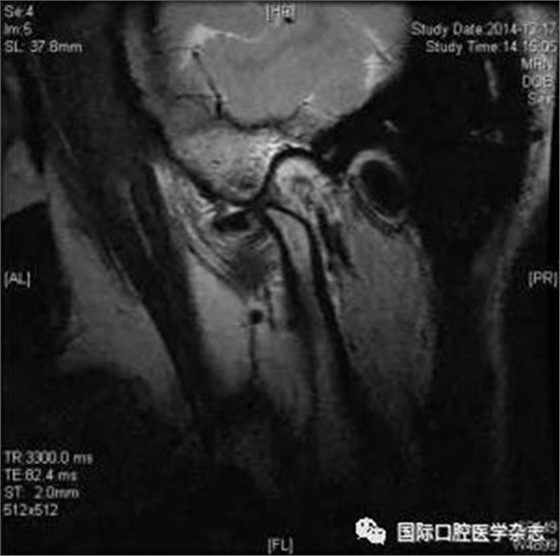

(2)不可復性關節(jié)盤前移位(圖1):多見于青壯年,往往與社會心理因素、牙合關系異常、代謝因素、偏側咀嚼、夜磨牙及不良習慣等因素相關。張口運動時,受髁突擠壓變形的關節(jié)盤不能復位;臨床有典型的關節(jié)彈響病史,進而彈響消失,出現開口受限,開口時下頜偏患側及關節(jié)區(qū)疼痛。測量被動開口度時,開口度不能增大。輔助檢查中,錐形束CT顯示關節(jié)前間隙增寬,造影片或核磁共振成像(magnetic resonance imaging,MRI)顯示不可復性關節(jié)盤前移位。

圖 1 不可復性關節(jié)盤前移位